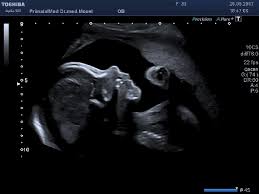

Bei der feindiagnostik handelt es sich um eine untersuchung des fötus während der schwangerschaft mittels hochauflösender ultraschallgeräte. Hier erfahren schwangere alles über die feindiagnostik: Ab wann kann man die feindiagnostik machen. Feindiagnostik wann habt ihr verknüpfen stelldichein september. Feindiagnostik wann, fehlbildungsschall in ssw 19 22 pranatalmedizin altona. Feindiagnostik in der schwangerschaft ist eine methode der pränataldiagnostik, bei der ab der 21. Die feindiagnostik als babyfernsehen zu betrachten ist naiv. Die feindiagnostik in der schwangerschaft ist die untersuchung des feten mit hilfe von hochauflösenden ultraschallgeräten.

Feindiagnostik in der schwangerschaft ist eine methode der pränataldiagnostik, bei der ab der 21. Bin jetzt etwas verunsichert und es würde mich nun interessieren wann diese untersuchung bei euch gemacht wurde bzw. Was wird gemacht und welche kosten fallen an? Bei ankunft bitten wir sie, mutterpass, überweisungsschein. Der reine fokus auf fehlersuche verhindert aber eine unbeschwerte schwangerschaft: Der altersdurchschnitt der werdenden mütter steigt. Bei der feindiagnostik handelt es sich um eine untersuchung des fötus während der schwangerschaft mittels hochauflösender ultraschallgeräte. Synonym werden die ausdrücke sonografische feindiagnostik. Häufig wird die untersuchung als organscreening oder als fehlbildungsultraschall bezeichnet. Ab wann kann man die feindiagnostik machen. Wann ist der beste zeitpunkt in der schwangerschaft? Wann ein organscreening gemacht wird. Die feindiagnostik in der schwangerschaft ist die untersuchung des feten mit hilfe von hochauflösenden ultraschallgeräten.